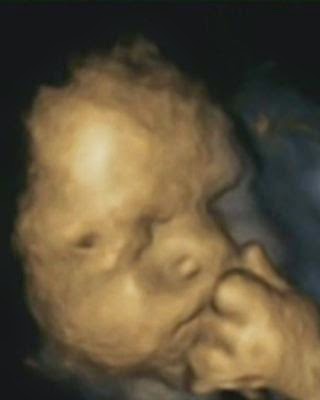

It ought to be the most tranquil of sights – the face of an unborn child in  the womb. But the tiny hand pulled up to the chin reveals that, upsettingly, this baby appears to be under stress. The remarkable image was taken as part of a study showing unborn children touch their faces more often if their mother has been anxious, helpless or under pressure.

Although previous studies have found babies pick up on stress in the womb, this is believed to be the first to offer  photographic evidence.

Researcher Nadja Reissland from Durham University gave 15 mothers-to-be 4D ultrasound scans four times during their pregnancy.

Rather than the grainy, ‘flat’ images produced by the 2D scanners usually used by the NHS, a 4D machine stitches together pictures taken from a variety of angles to create clear three-dimensional pictures.